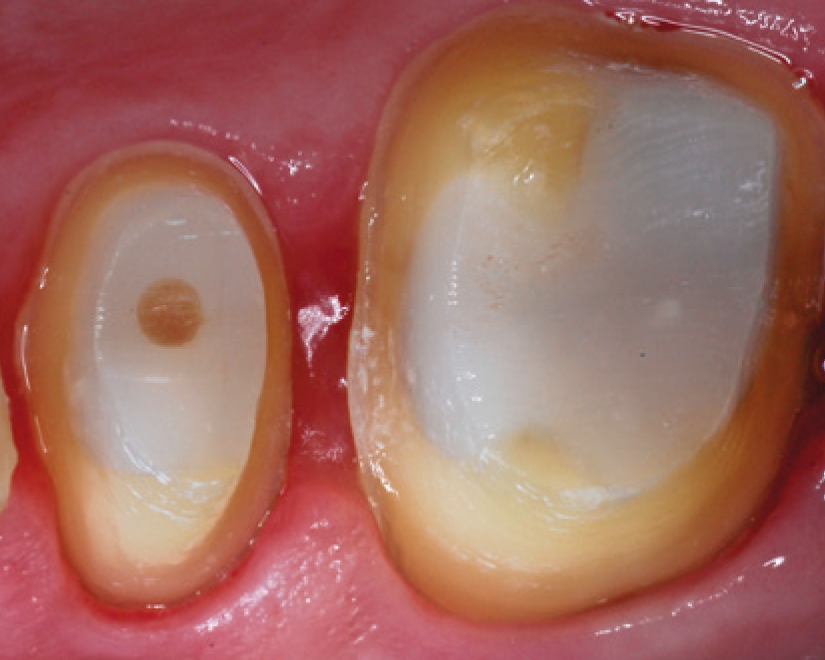

"SDR® Plus Bulk Fill Flowable ensures a tight seal of the endodontic access cavity – an important factor for long-term endodontic treatment success."

Prof. Dr. Schirrmeister, University of Freiburg, Germany

SDR® Plus Bulk Fill Flowable can be used in a variety of indications including Class I, II, III and V, primary posterior dentition, pit and fissure sealing and core build-up.

SDR® Plus is indicated for a variety of dental procedures, including the filling of Class I, II, III and V cavities, pit&fissure sealing, and even core build-ups before placing a crown. It is applied in its flowable state through injection from a syringe, or a small capsule called “Compula Tip”. After placement, SDR® Plus gets light cured by the application of blue light (440 – 480 nm wavelength) from a dental polymerization light. This allows the material to create a dense molecular network and replace the tooth substrate that was drilled away as a permanent restoration.